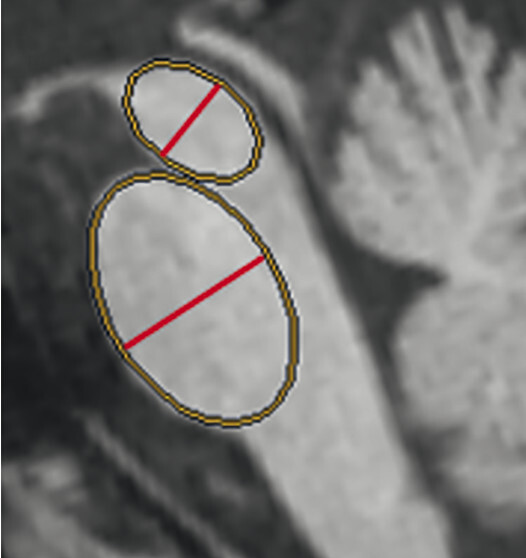

67-jährige Patientin mit über Jahre progredienter Verschlechterung des Gleichgewichts, Schluckstörungen und Sprechstörungen. In der T1w 3-D-Sequenz zeigt sich eine ausgeprägte Atrophie des Pons (a, Pfeil), der mittleren Kleinhirnstiele (b, Pfeile) und des Kleinhirns. Diese Veränderungen werden durch die Ganzhirnvolumetrie bestätigt (c): Anomale Regionen der grauen Substanz (mindestens 2 Standardabweichungen unter dem vergleichbaren Volumen des gesunden alters- und geschlechtsgematchten Normkollektivs) sind blau überlagert. Anomale Liquorvolumina (mindestens 2 Standardabweichungen über dem vergleichbaren Volumen des gesunden alters- und geschlechtsgematchten Normkollektivs) sind als rote bis gelbe Überlagerungen auf das individuelle Patientengehirn projiziert. MRT-morphologisch lässt sich somit die Verdachtsdiagnose Multisystematrophie vom zerebellären Prädominanztyp bestätigen.

a Sagittale T1w 3-D-MRT-Sequenz.

b Axiale T1w 3-D-MRT-Sequenz.

c Voxel- und regionenbasierte Analyse.